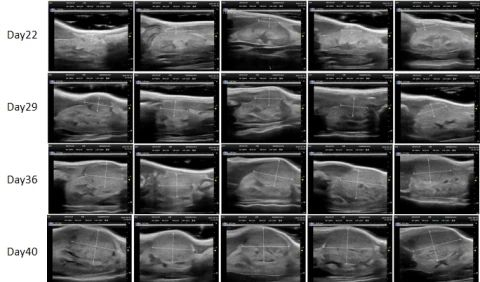

部分HJC黄金城平台PDX原位模型展示